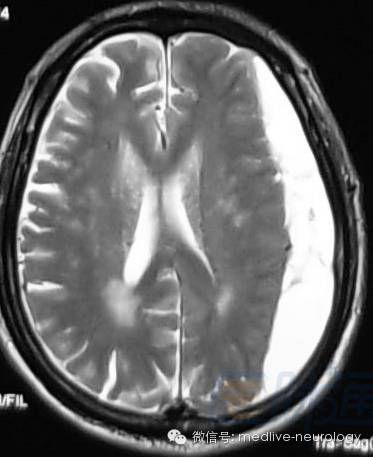

急性期(1-3d):右枕叶